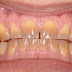

| Làm trắng răng bị nhiễm tetracycline |

Tetracycline là loại thuốc kháng sinh được tiêm phòng cho trẻ em dưới 8 tuổi hoặc được chị em phụ nữ sử dụng trong thời kỳ mang thai. Loại kháng sinh này tác động khá mạnh vào hàm răng dẫn tới tình trạng sẫm màu răng (có thể nguyên hàm hoặc vài chỗ nhất định trên răng), nặng hơn có thể làm tổn thương và gây khiếm khuyết trên răng.

Răng bị nhiễm tetracycline là tình trạng rất dễ gặp hiện nay. Tình trạng này có thể làm người mắc phải cảm thấy tự ti. Bởi “cái răng cái tóc” là các yêu tố vô cùng quan trọng để đánh giá vẻ đẹp của con người. Tuy nhiên, nếu không may gặp phải tình trạng trên, bạn cũng đừng quá lo lắng. Hiện nay, cùng với sự phát triển của khoa học công nghệ, nhiều kỹ thuật bảo vệ, chăm sóc và làm đẹp răng ra đời và được nhiều khách hàng tin chọn, trong đó có kỹ thuật làm trắng răng bị nhiễm Tetracycline.